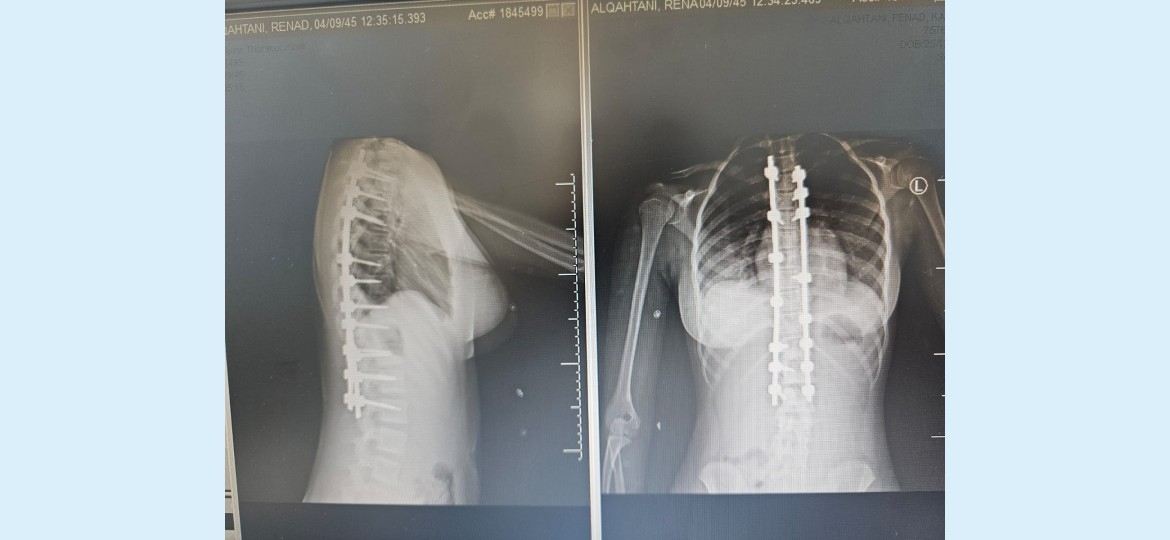

نجح فريق طبي متخصص في قسم جراحة العمود الفقري بمستشفى الملك عبدالله في بيشة من أجراء عملية (جنف) لطفلة تبلغ من العمر 13 سنة، وذلك بعد معاناتها من تشوه بالظهر منذ الولاده.

وأوضح تجمع عسير الصحي نطاق بيشة ، أن الطفله حضرت إلى المستشفى وبعد عمل الأشعة والتحاليل اللازمة شٌخصت الحالة على أنها جنف شديد مع وجود صعوبة في أداء وممارسة الأنشطة اليومية ومشكلات في النوم نتيجة إصابتها بانحرافٍ شديدٍ في العمود الفقري (الجنف) منذ الطفوله.

وأضاف التجمع : انه وبعد دراسة ملف الطفله قرر الفريق الطبي المعالج ، المكون من الدكتور صالح ال خبتي استشاري جراحة العمود الفقري، والدكتور احمد البنداري أخصائي جراحة العمود الفقري والدكتور اكينبو أخصائي جراحة العمود الفقري، والدكتوره نادر بدوي استشاري تخدير من أجراء عملية التدخل الجراحي لعلاج هذه العيوب والحد من المضاعفات، حيث تمّ إجراء عملية استقامة العمود الفقري بشكل عمودي وتثبيت ودمج الفقرات، بعد ذلك خضعت المريضة لبرنامج علاج طبيعي مكثّف لتقوية عضلات الظهر والفقرات.

الجدير بالذكر أنه وبمتابعة الطفلة من قبل فريق العمل الجراحي فقد خرجت من المستشفى وهي تتمتع بصحة جيدة واعطيت مواعيد في العيادة للمتابعه.